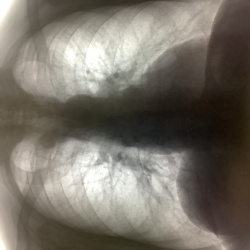

Флг, 15 лет, справа в кардиодиафрагмальном углу суммация рёбра и НПВ? Или всё же липома?